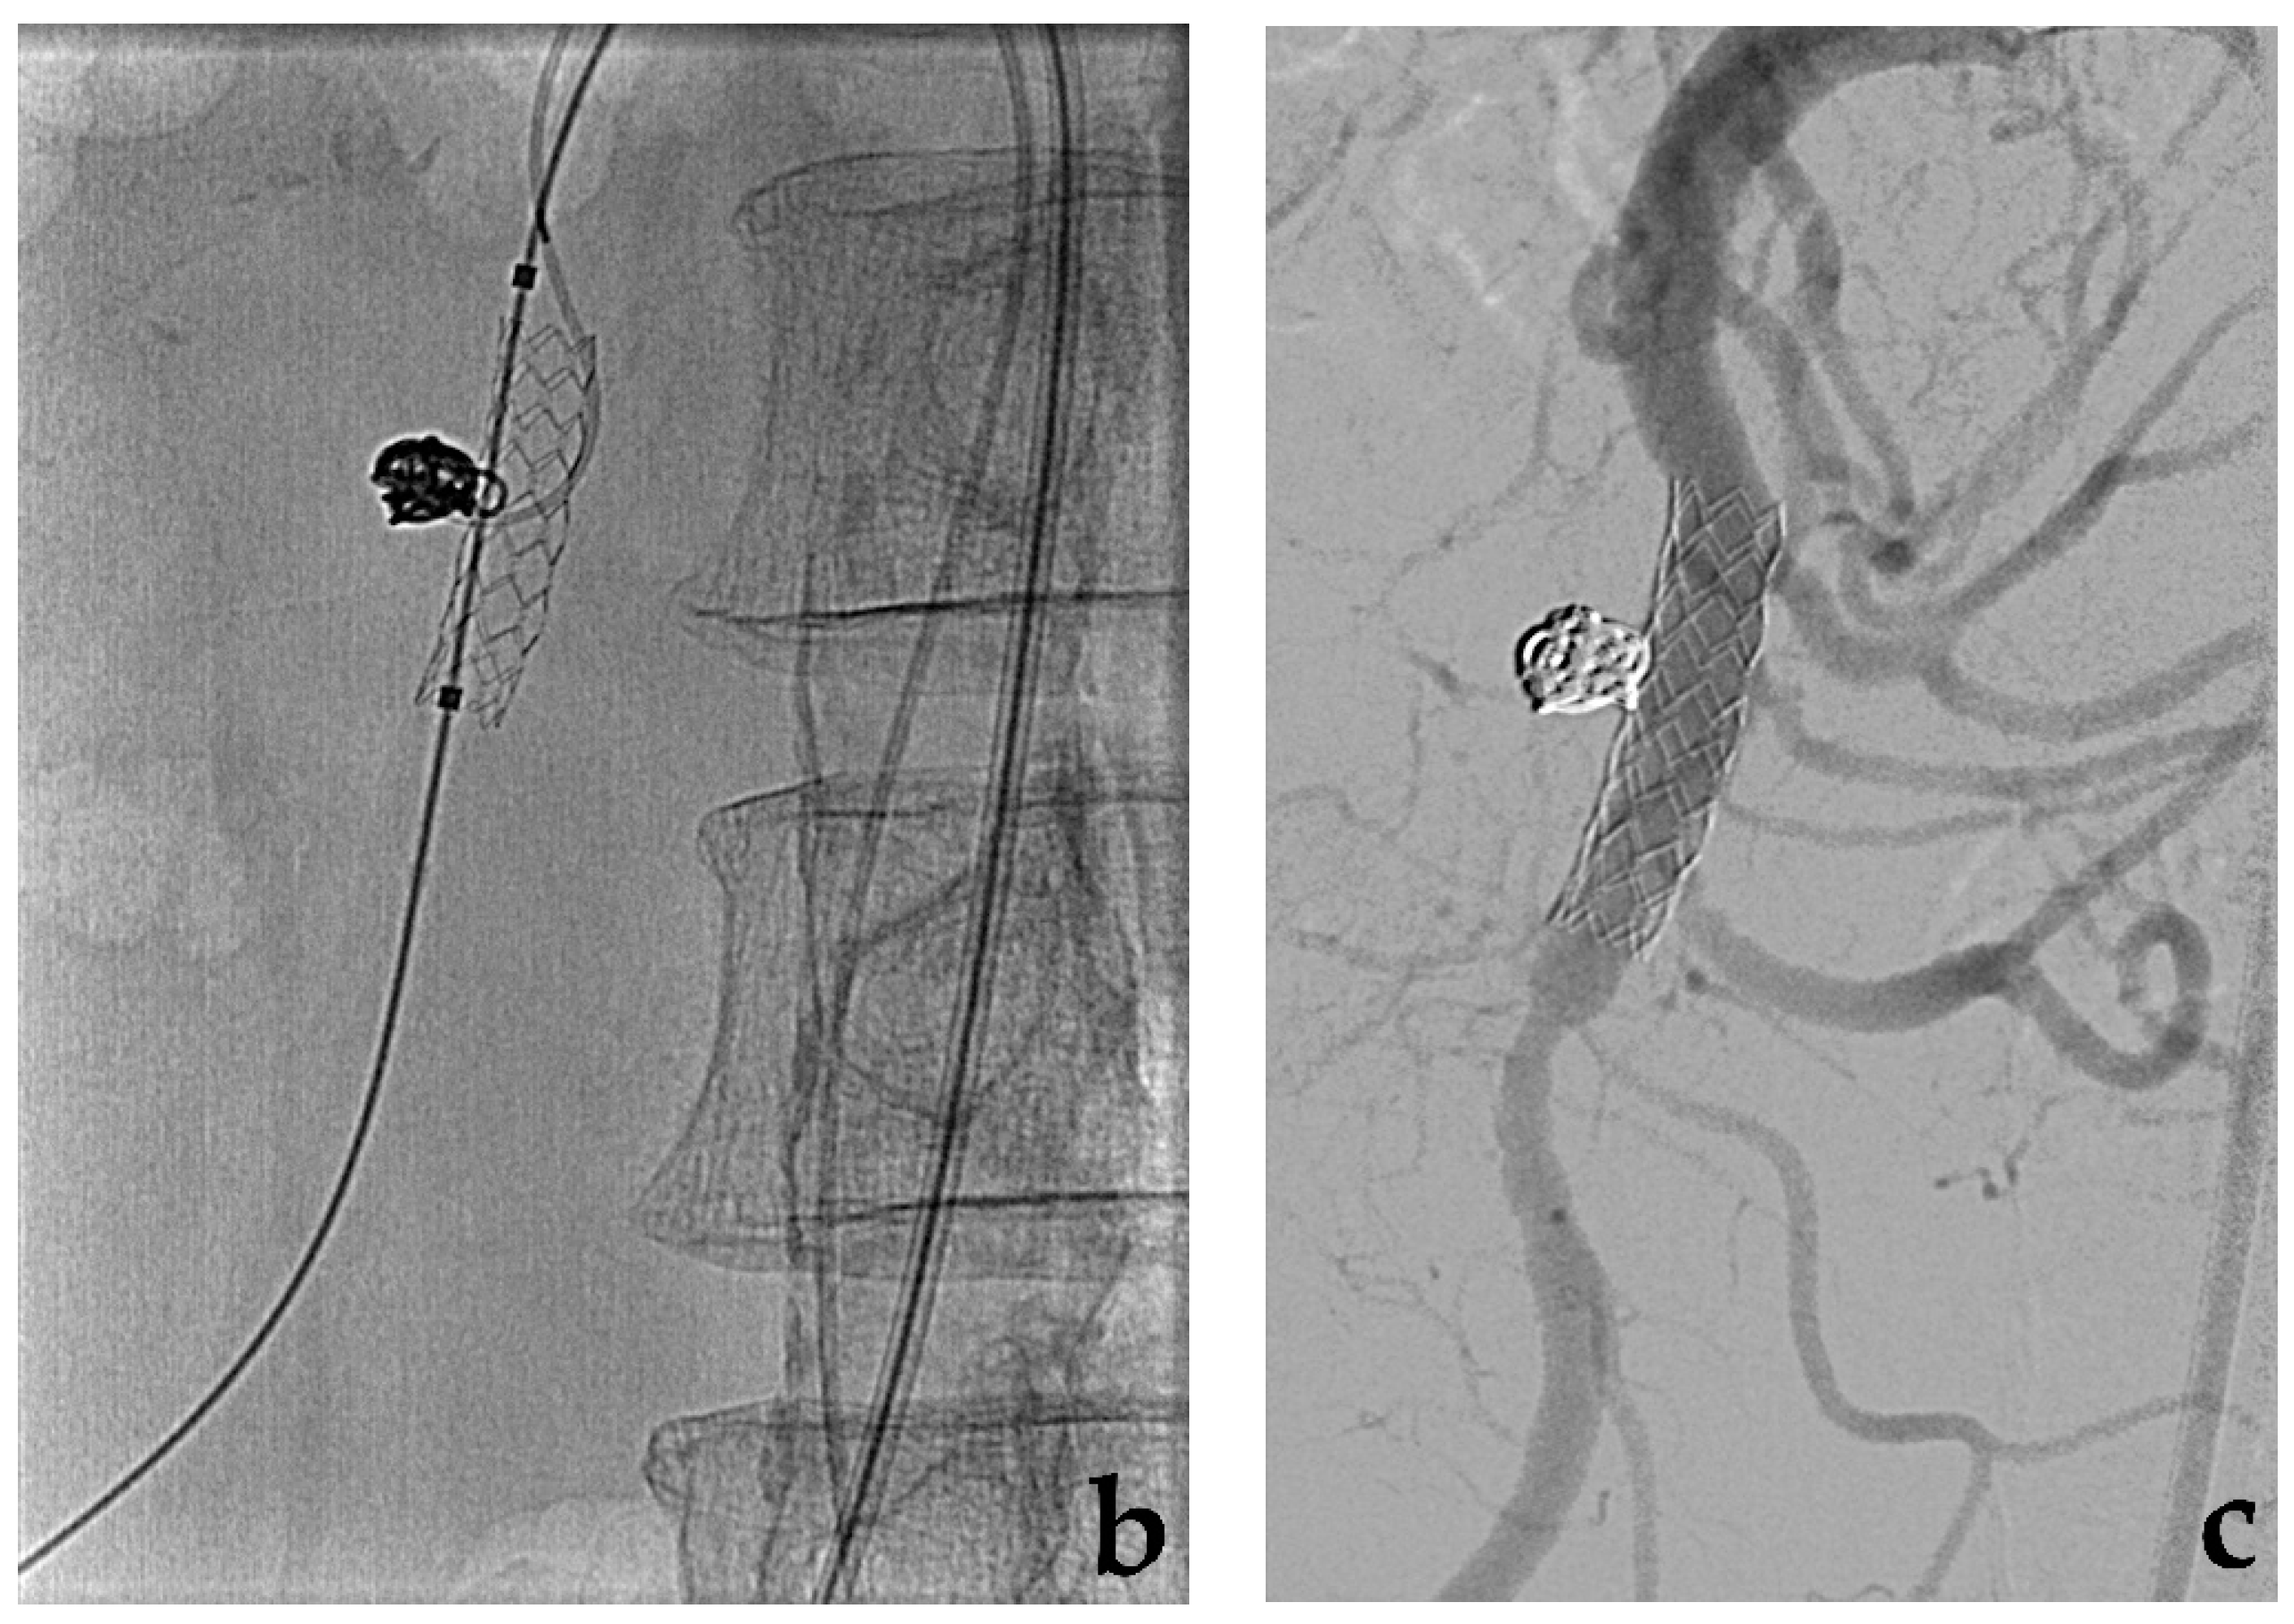

- Colombi, D.; Bodini, F.C.; Bossalini, M.; Rossi, B.; Michieletti, E. Extracranial visceral artery aneurysms/pseudoaneurysms repaired with flow diverter device developed for cerebral aneurysms: Preliminary results. Ann. Vasc. Surg. 2018, 53, 272.e1–272.e9. [Google Scholar] [CrossRef] [PubMed]

- Rabuffi, P.; Bruni, A.; Antonuccio, E.G.M.; Ambrogi, C.; Vagnarelli, S. Treatment of visceral artery aneurysms and pseudoaneurysms with the use of cerebral flow diverting stents: Initial experience. CVIR Endovasc. 2020, 3, 48. [Google Scholar] [CrossRef]

- Zhang, Y.; Xiang, D.; Lu, Q.; Wu, M.; Cui, J.A. systematic review and meta-analysis of the performance of flow-diverting stents in the treatment of peripheral and visceral artery aneurysms. Catheter. Cardiovasc. Interv. 2021, 97, 461–469. [Google Scholar] [CrossRef]